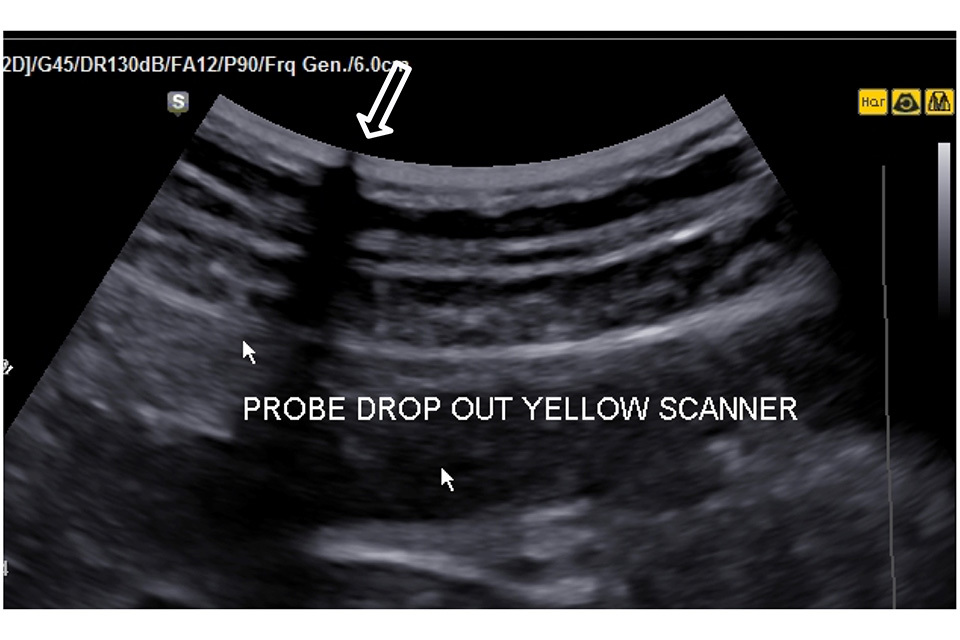

Look at the uniformity of the dry in air reverberation pattern to check for irregularity that might indicate element drop out or transducer damage such as obvious disruption of the reverberation pattern (the bright parallel lines running across the image). These faults may be evident during imaging (Figure 2).

Figure 2. There is a transducer transmission fault at the point shown by the large arrow resulting in a significant loss of image along the transmission line. This probe should be removed from service and repaired or replaced